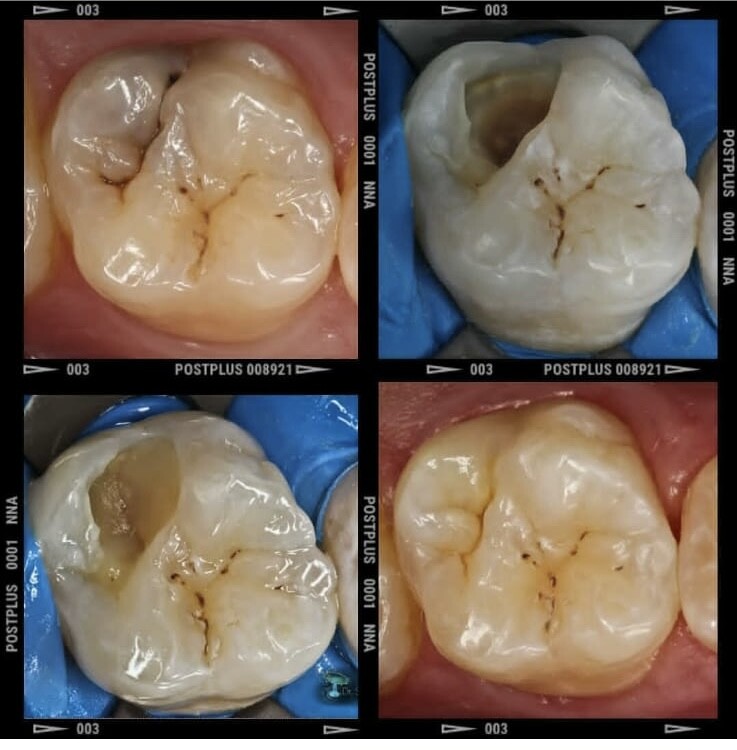

Каждая наша работа - это шедевр. Мы создаем эстетику!

Лечение зубов

Лечение кариеса

Пломбирование зубов

Реставрация зубов

Пломбы быстро выпадали или были неэстетичными, под пломбами возникал кариес, под коронками портились зубы, после лечения корневых каналов возникали кисты, после снятия брекетов зубы опять разъезжались.